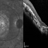

- infrared image, optical coherence tomography (OCT), macular coloboma

- Infrared and OCT images of the right eye of a 25-year-old woman with bilateral macular colobomata and pigmentary retinopathy similar to Leber's congenital amaurosis.